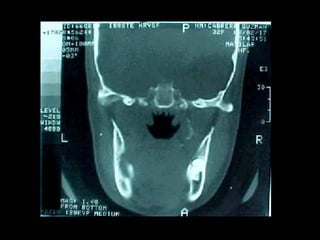

Osteomielitis

La osteomielitis es una infección súbita o de larga data del hueso o médula

ósea, normalmente causada por una bacteria piógena o micobacteria y

hongos. Los factores de riesgo son trauma reciente, diabetes, hemodiálisis y

drogadicción intravenosa.

La Osteomielitis se define como una inflamación extensa del hueso,

implicando a toda porción esponjosa, medular, cortical, periostio, vasos

sanguíneos, nervios y epífisis. La inflamación puede ser aguda, subaguda o

crónica y presenta un desarrollo clínico diferente según su naturaleza (1-5).

En el caso de los maxilares se considera la infección odontógena como la

causa más frecuente de osteomielitis. Se puede presentar a cualquier edad

con un predominio entre los hombres. Afecta principalmente al maxilar

inferior. En el maxilar superior es más raro, debido a una mayor

vascularización .